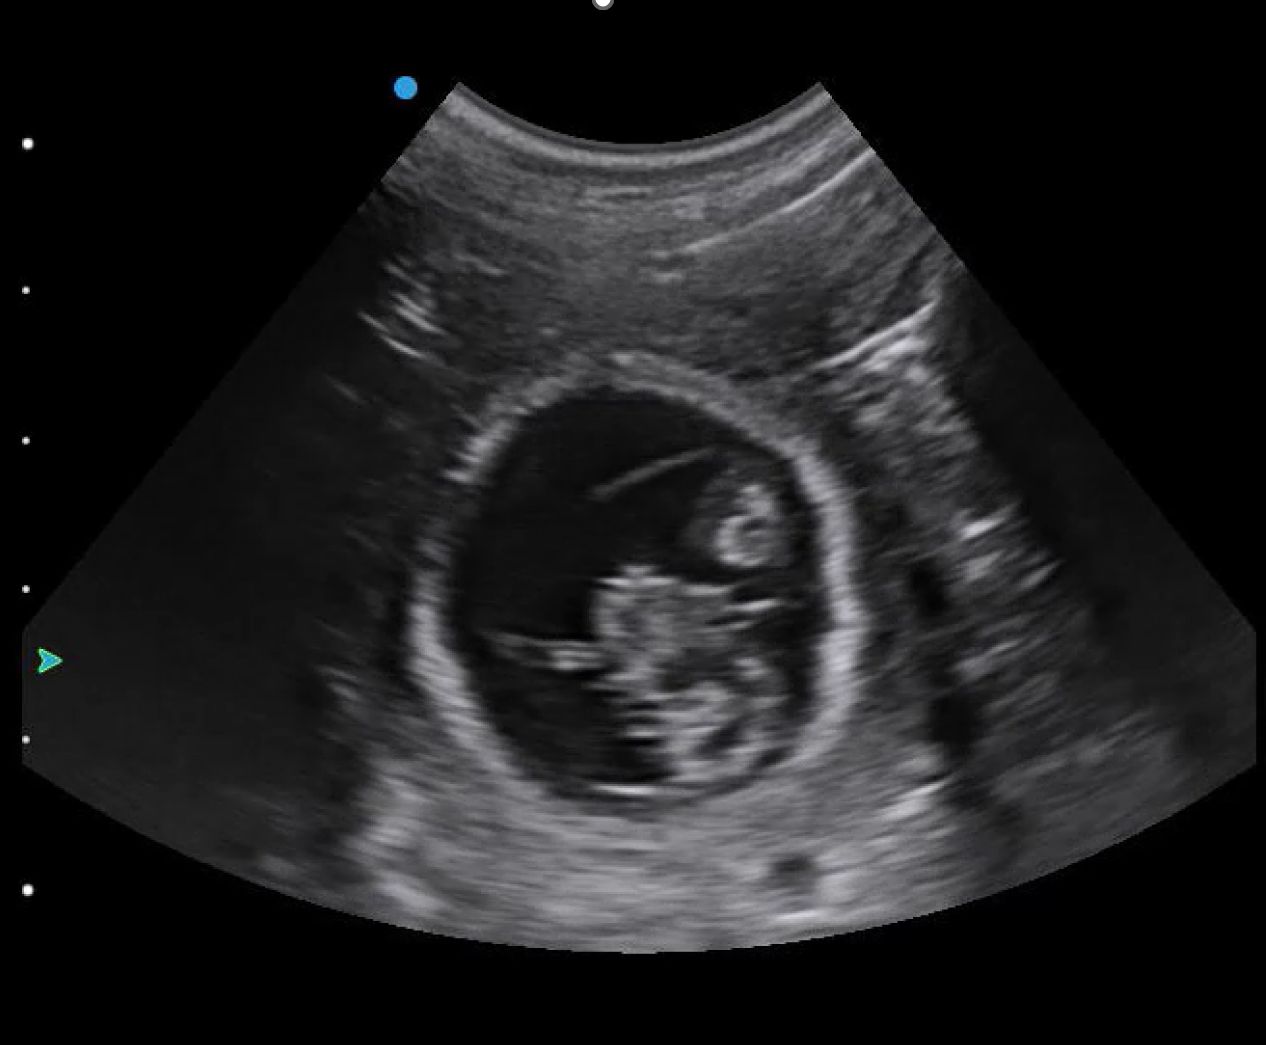

You will likely begin with your depth on its default setting or increased for larger breeds of dog. Once you find a gestation sac (Figure 1), you should optimise your image by reducing your depth and ensuring your focal point is at the level of the foetus. This will allow you to confirm the presence of a heartbeat.

Image optimisation is key to visualising foetal heartbeats in early pregnancy. Later in gestation, foetal movement should also be easy to observe.